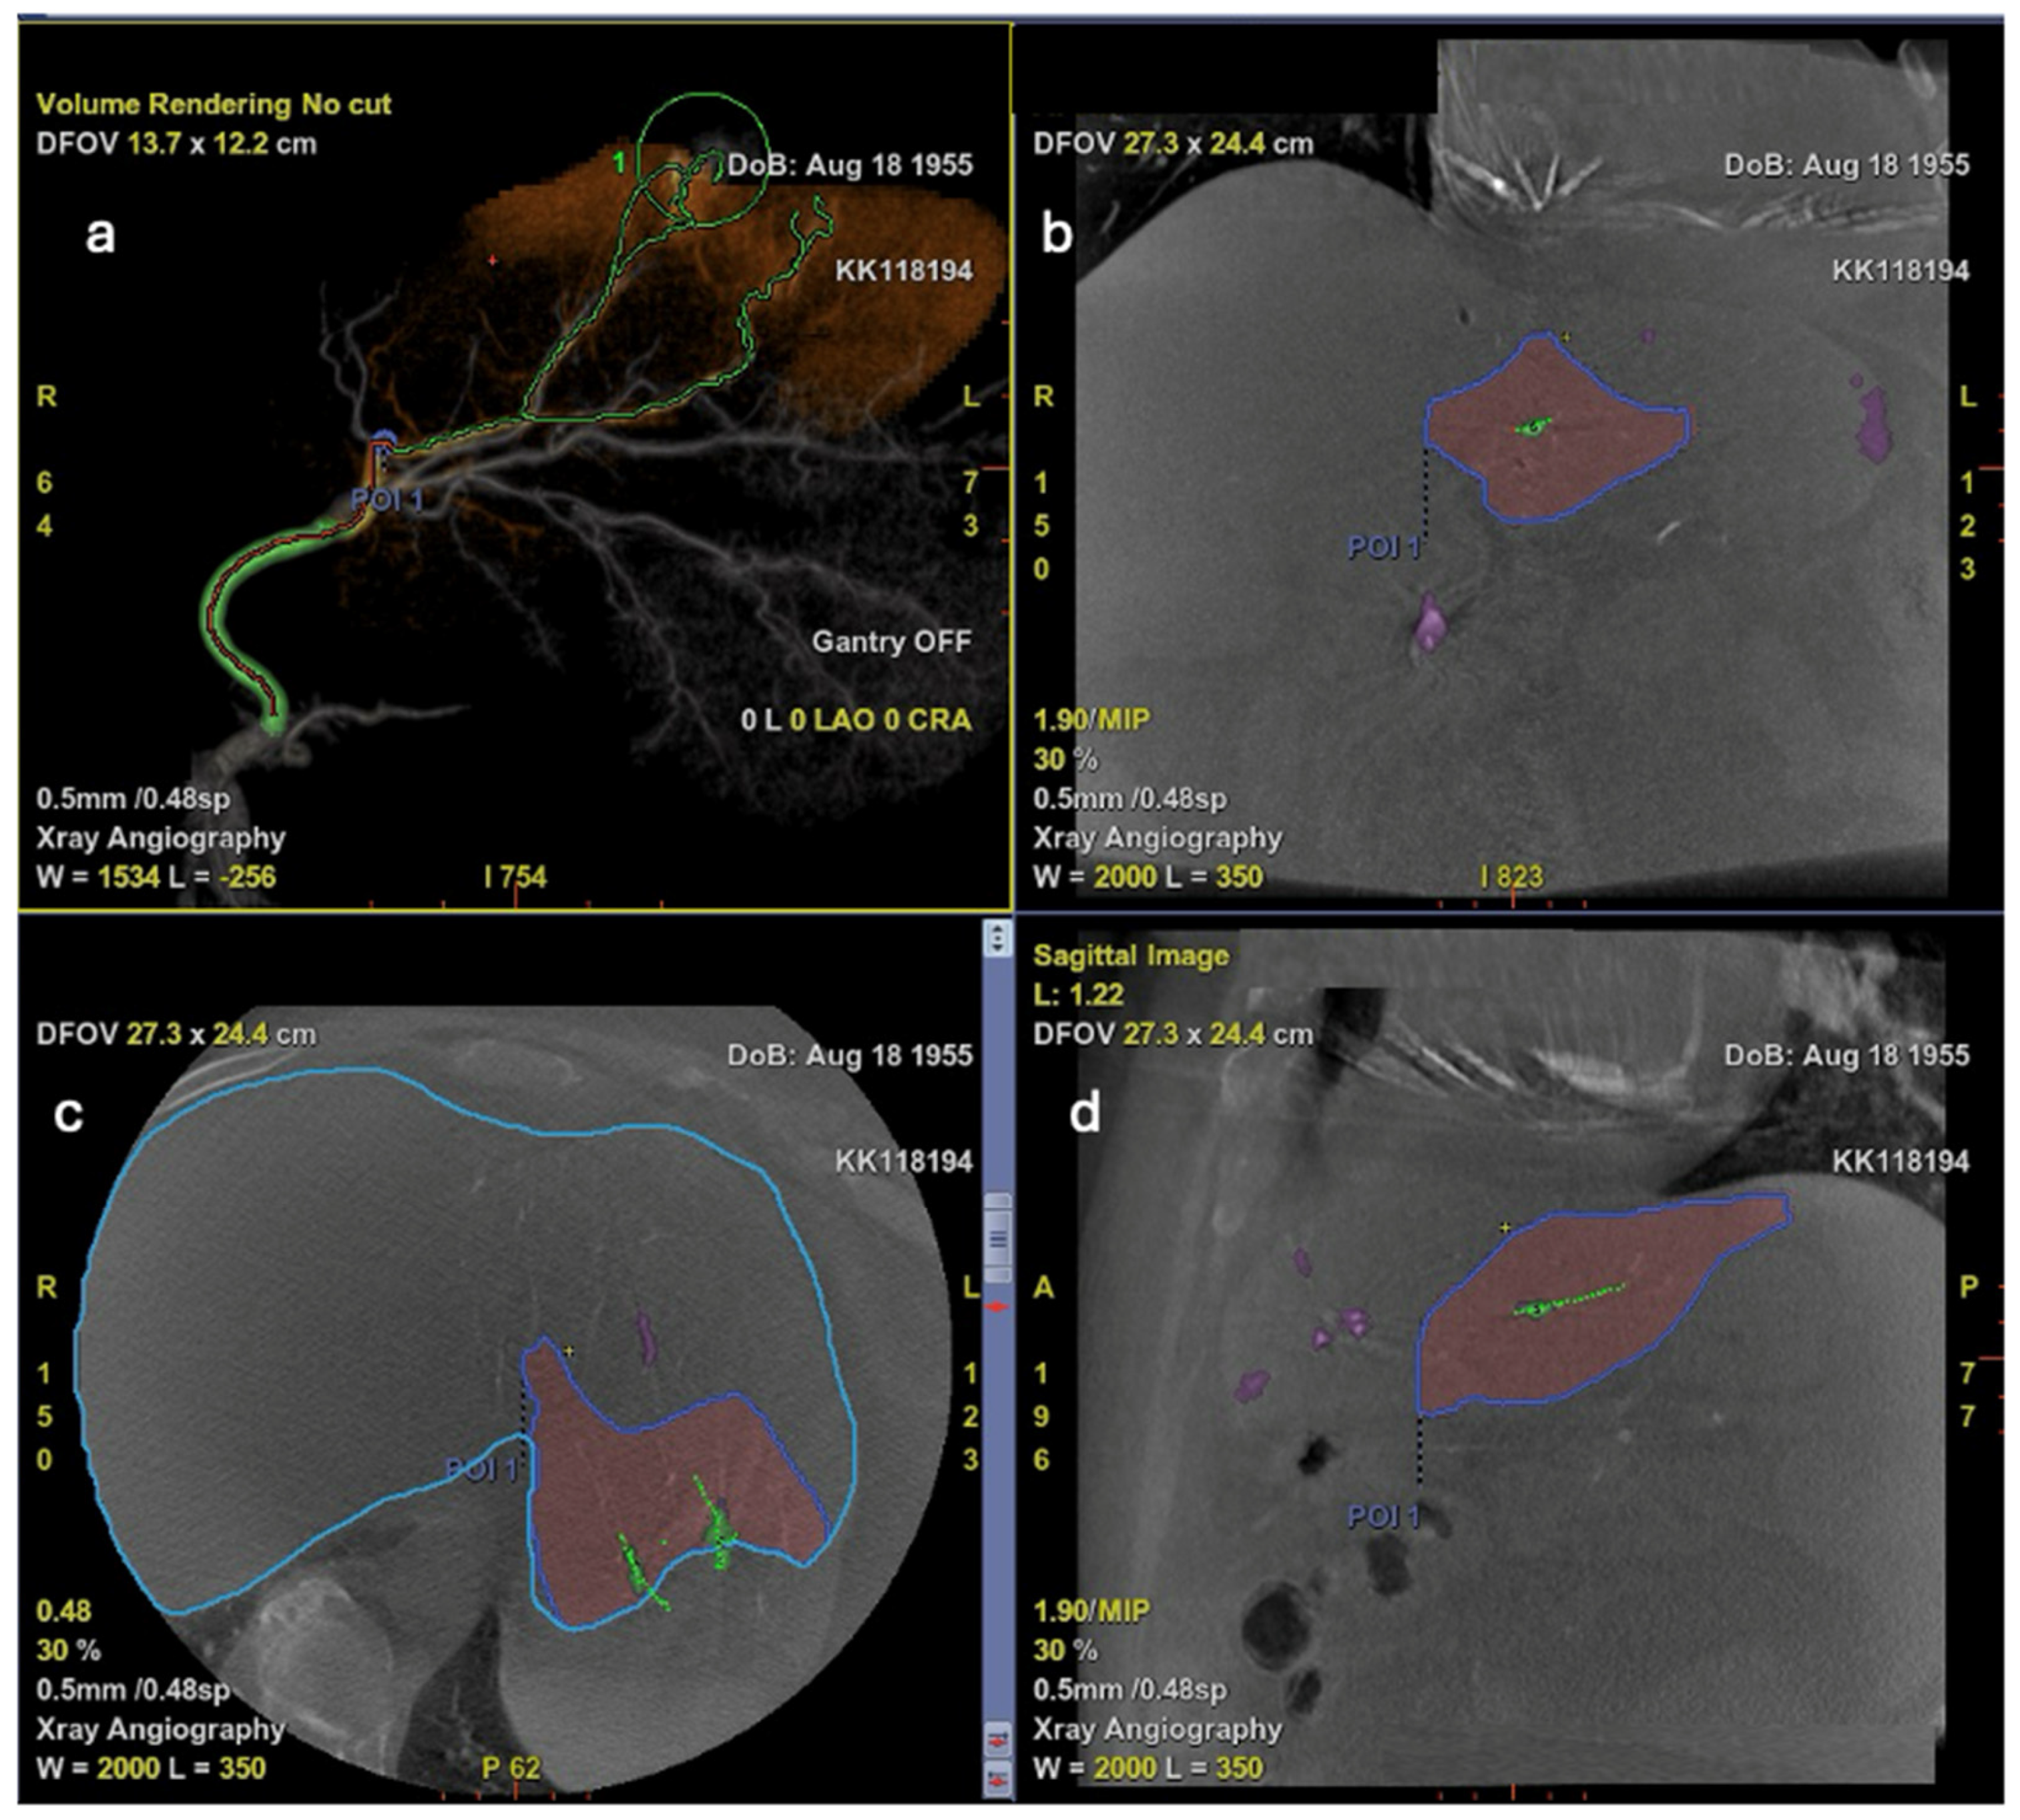

6. Additive Role of Cone-Beam CT